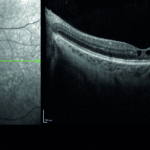

Fig. 3. Scansioni OCT periferiche.